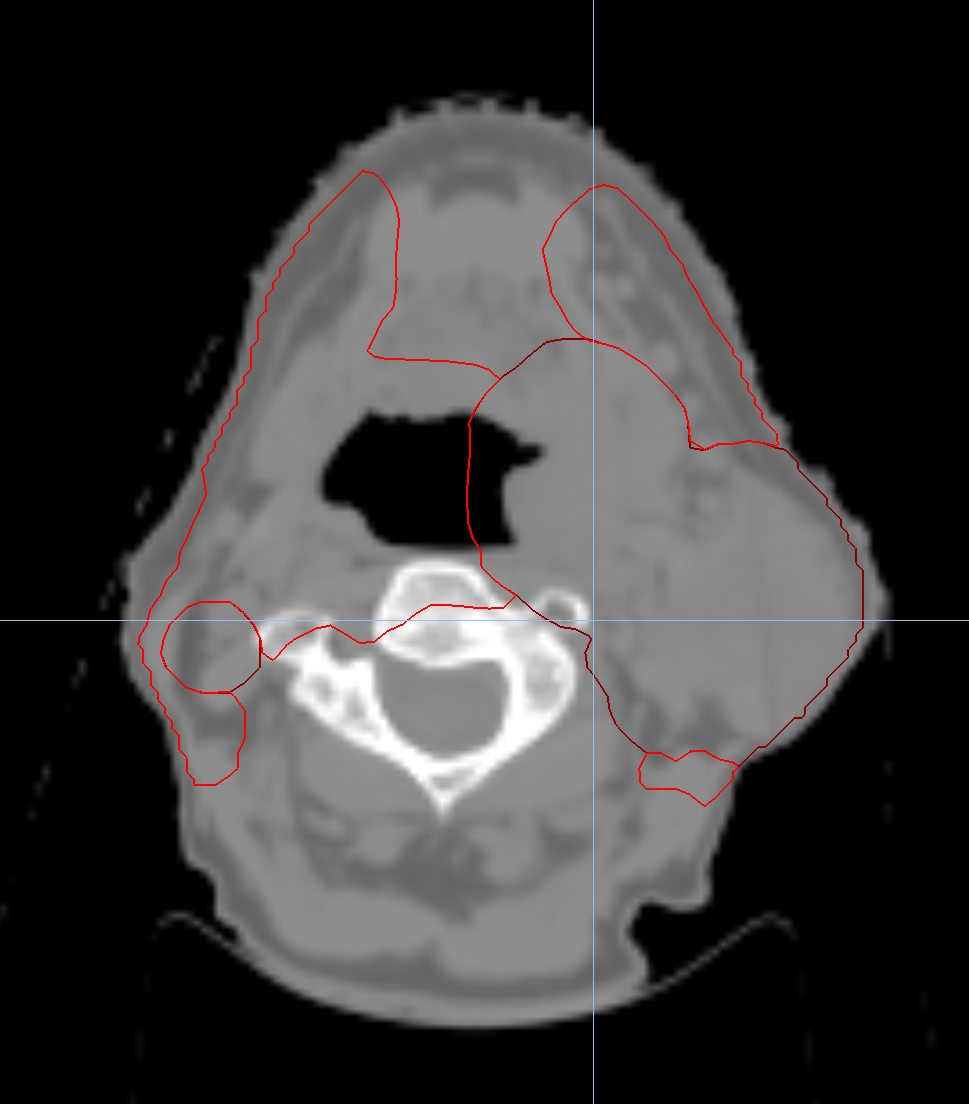

Left Breast with Deep Inspiration Breath Hold

< View All Plan Studies RADIXACT SYSTEM Left Breast with Deep Inspiration Breath Hold Case History AGE: 76-year-oldGENDER: Male Medical History Immidiate tolerance: Grade II dermatitis with eyelid edema, Grade I conjunctivitis resolved with Sterdex Diagnosis: Squamous cell carcinoma of the right lower eyelid Planning CT Images Treatment Plan Images